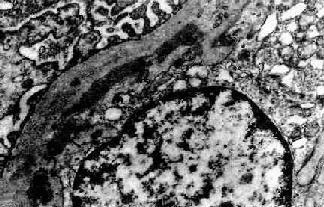

电镜观察可见肾小球系膜增生,毛细血管基底膜不规则增厚。增生的系膜组织沿毛细血管基底膜和内皮细胞之间向毛细血管周围部分伸展,甚至环绕全部毛细血管壁,使毛细血管壁增厚。肾小球内有大量电子致密物沉积。根据沉积物的部位,可将膜性增生性肾小球肾炎分为3型:

Ⅰ型电子致密物沉积在肾小球基底膜内侧,内皮细胞下,大小不等,常聚积成大团块状(图12-14,图12-15)。系膜内和上皮细胞下偶然也可见有少量小而不规则的沉积物。

图12-15 膜性增生性肾小球肾炎 Ⅰ型

肾小球毛细血管基底膜内侧,内皮细胞下电子致密沉积物,部分上皮细胞足突消失